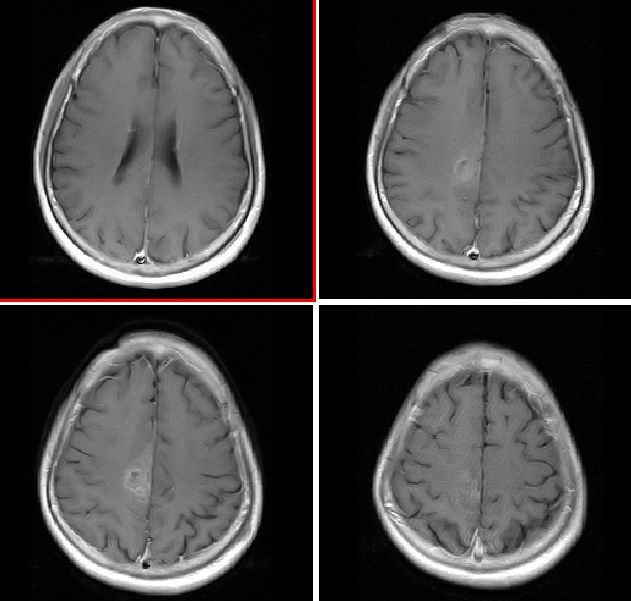

mri增强

mr表现:中央旁小叶区病灶号不均匀性稍长t1、长t2信号,病灶周边见稍短t1信号环。右侧脑室体旁见点片状等t1、稍长t2信号影。flai序列各病灶均呈高信号。增强后右侧中央旁小叶区病灶呈不均匀性强化。

右侧中央旁小叶结节样占位,边界清楚,周围未见明显水肿,t1wi呈低信号,t2wi呈高信号,增强扫描明显不均匀强化。未见流空畸形血管团及引流静脉,所以考虑海绵状血管瘤。低级别胶质瘤一般血脑屏障无破坏,强化不明显。